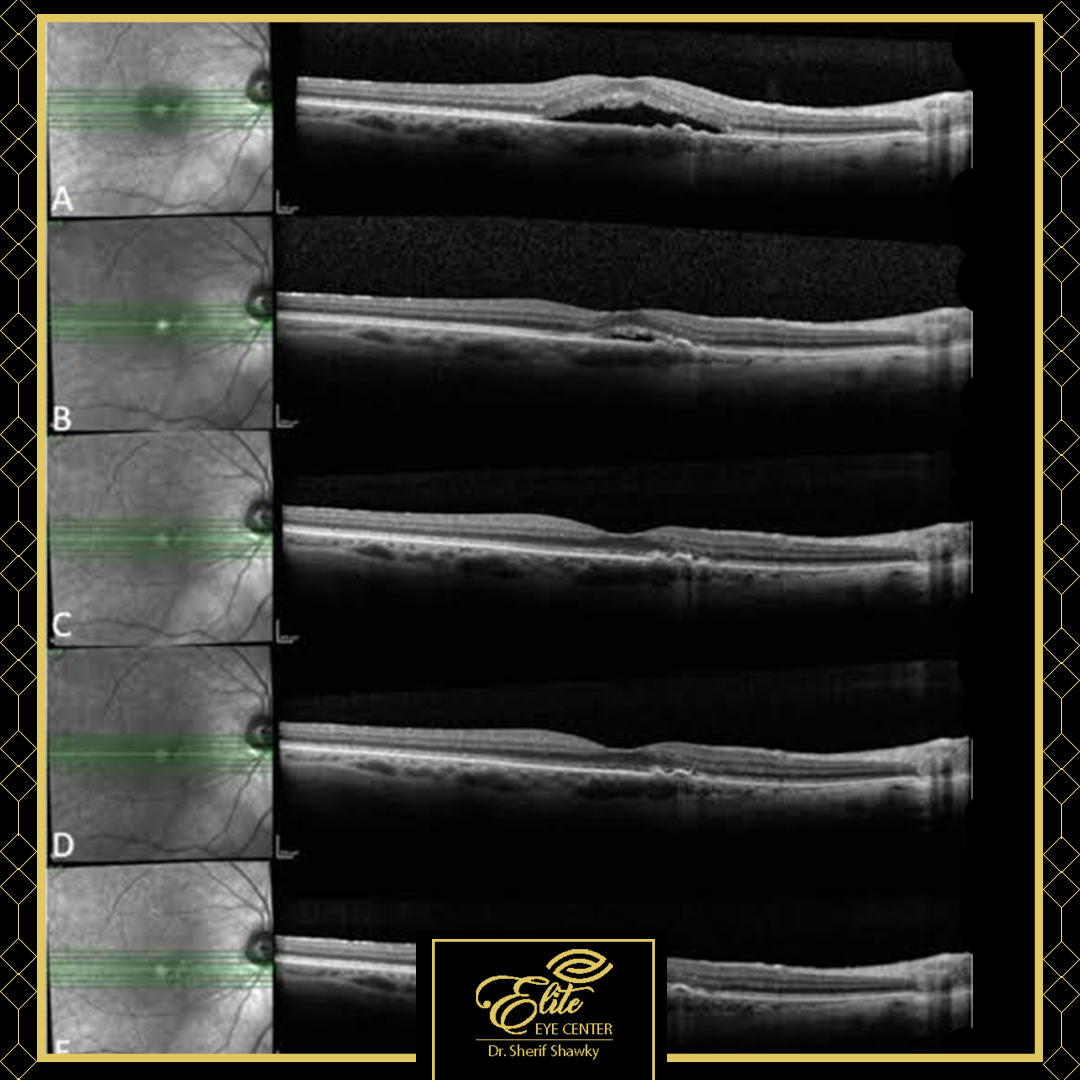

·استشاري جراحة الشبكية والجسم الزجاجي